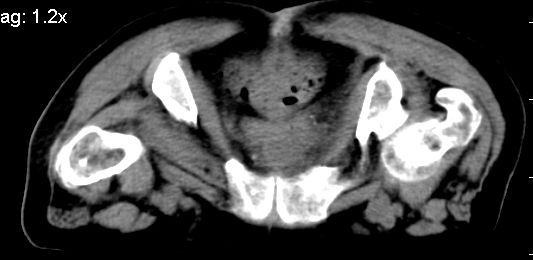

标题: CT10133:F、74岁,反复血尿10天。 [打印本页]

标题: CT10133:F、74岁,反复血尿10天。

膀胱充盈可,壁光滑厚薄尚均匀,其内下方可见不规则的致密影,建议做膀胱镜检查

膀胱癌突破浆膜可能性大

考虑膀胱癌可能性大伴双侧输尿管下端扩张.

膀胱后壁见不规则致密影,我们遇到这样的病人都再做一次俯卧位扫描;排出膀胱内凝血块。

1.膀胱后壁见不规则致密影,占位?膀胱内凝血块?建议俯卧位扫描、膀胱镜检查.

2.双侧输尿管下段扩张.

膀胱三角区不规整软组织改变,双侧输尿管扩张,所以占位性病变肯定首先考虑,建议改变体位扫描除外游离血块影,但老年人出血原因一定要查明。

1.膀胱后壁见不规则致密影,随体位改变,为膀胱内凝血块;

2.双侧输尿管下段扩张.输屎管结石可能大。建议作进一步检查。

双侧输尿管下端扩张,并膀胱内血凝块 输尿管下端结石